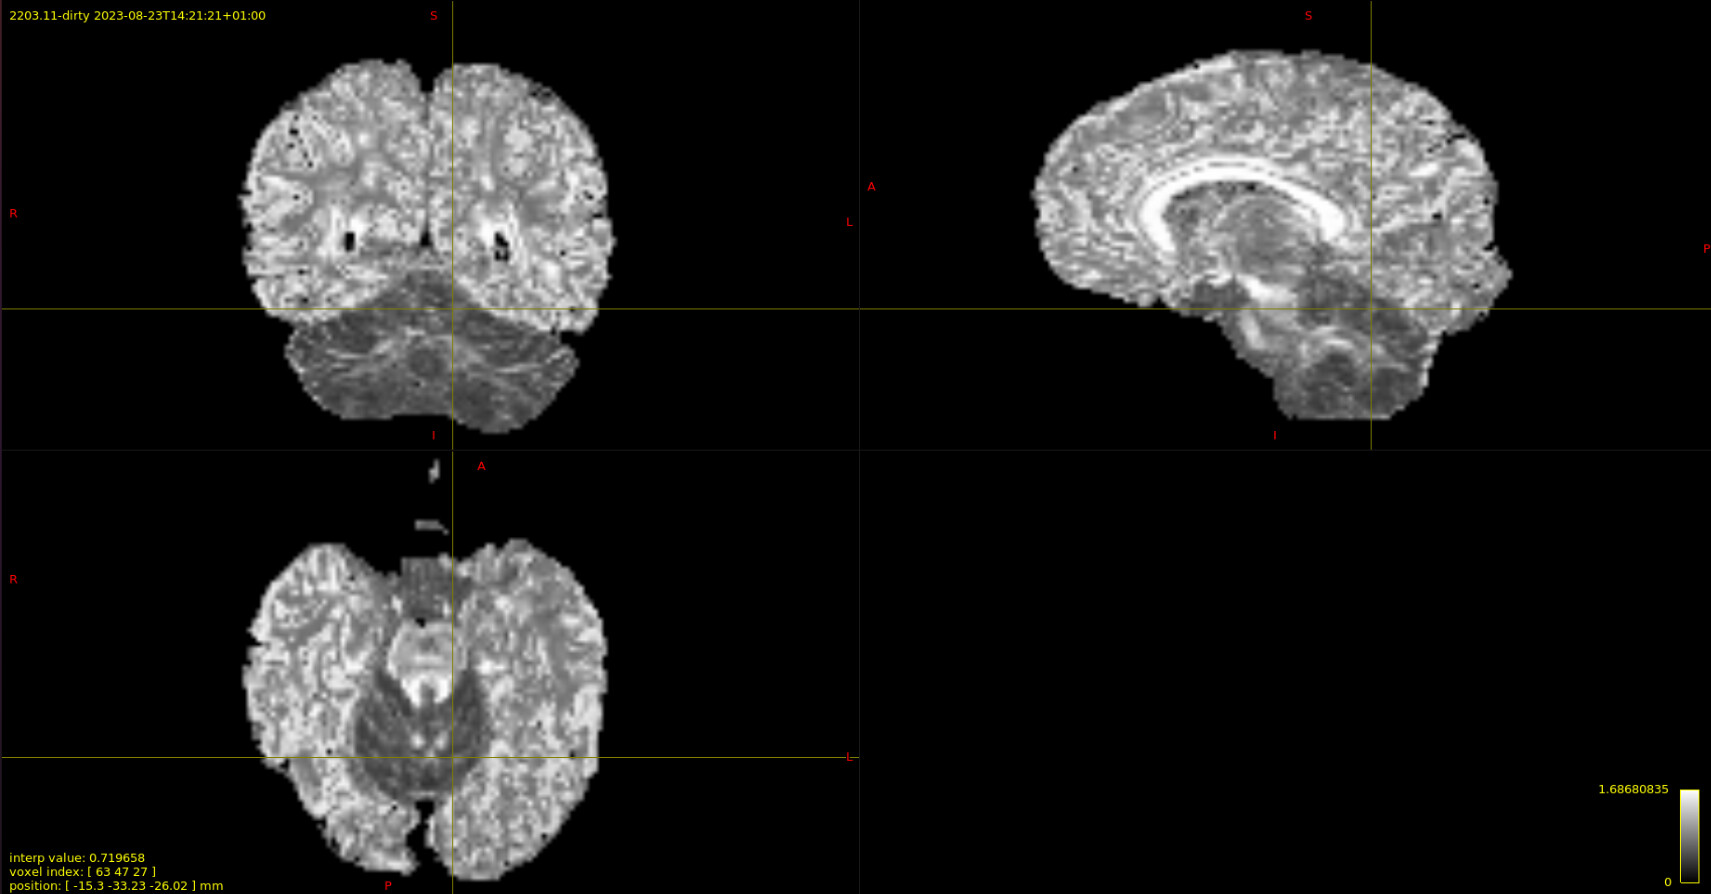

The output I got for this makes sense to me in the cerebellum but not so much in the cerebrum.

I would think the cortical grey matter would also be around the same intensity as the cerebellar grey matter but it is bright, even as bright as the corpus callosum or internal capsule so I’m leaning on that this is artifactual.